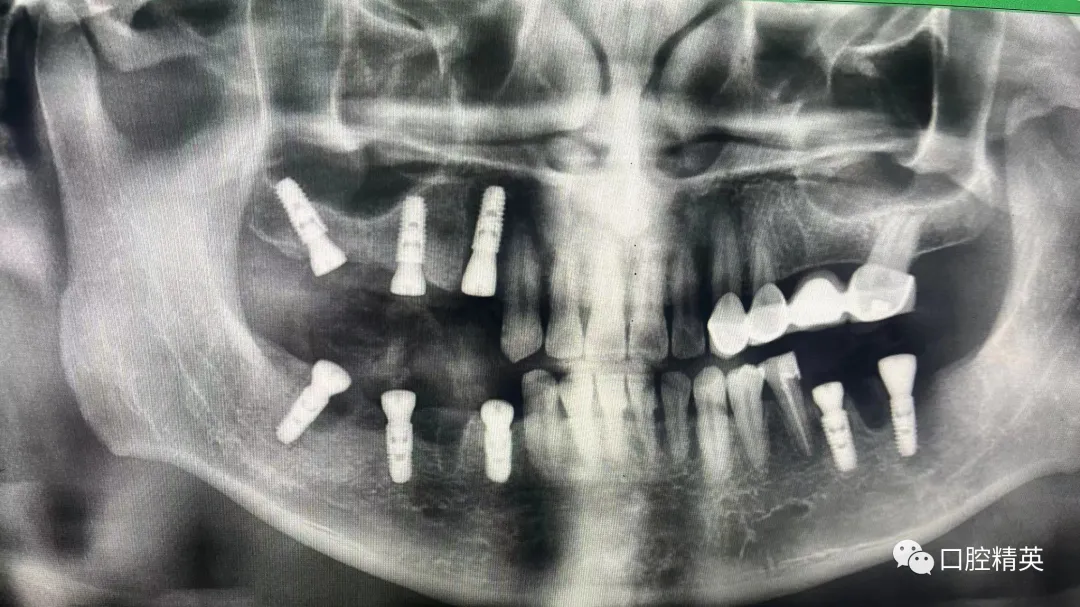

7、种植影像学分析;可以获得骨高度 ,骨宽度信息 ,甚至可以模拟种植体植入位点

六、学员回家后部分病例